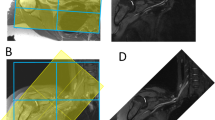

Schematic illustration of the procedure for determining the optimal number of atlases and optimal label fusion. (1) Twelve cadaver CT datasets were included, and one atlas was selected as a patient. (2) The 11 remaining atlases were used for deformable image registration on the patient. (3) Label fusion was performed with 2 up to 11 atlases, once using STAPLE and once using Patch. (4) For each number of atlases, the average Dice similarity coefficient (DSC), Jaccard index (JI) and True positive rate (TPR) were calculated for the generated contour (orange) with the gold standard contour (green). This procedure was repeated for every atlas as a patient